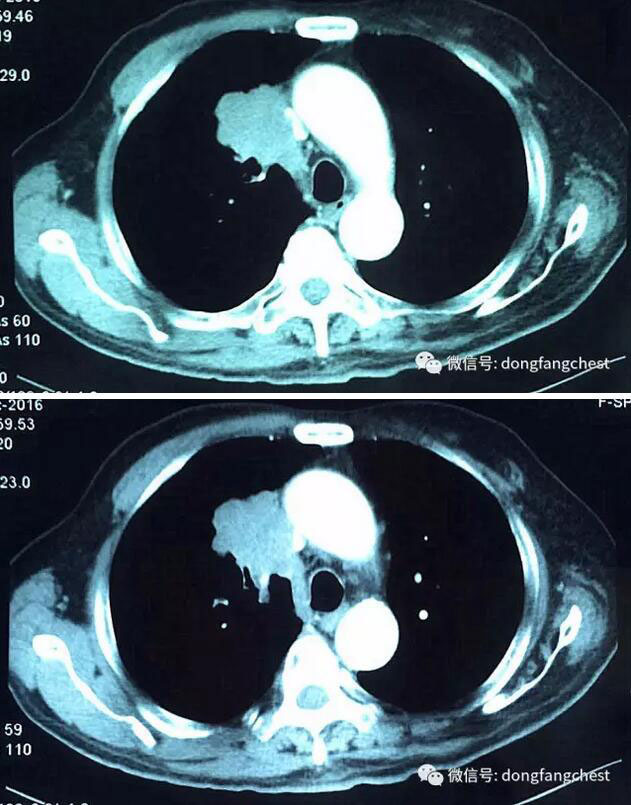

年近70岁的李老爷子,反复咳嗽了一个月不见好,于2016年12月在东方总院拍CT,检查发现”右肺上叶恶性肿瘤“。

由于肿瘤体积较大,且与肺动脉、上腔静脉关系紧密,手术实施起来较为困难,经过东方总院多学科讨论会诊,决定先于呼吸内科进行了2个疗程新辅助化疗。

化疗后,李老体内的肿瘤体积明显缩小,随后于2月22日进入总院心胸外科进行手术治疗。手术由总院胸外科朱胜主任、王鸿副主任、高涛涛医生共同完成。术中发现肿瘤侵犯右肺动脉干、上腔静脉部分血管壁。术中,经上腔静脉远端、右心房插管转流,阻断受肿瘤侵犯部位腔静脉后予以部分血管壁切除,然后取心包组织进行上腔静脉修补重建。